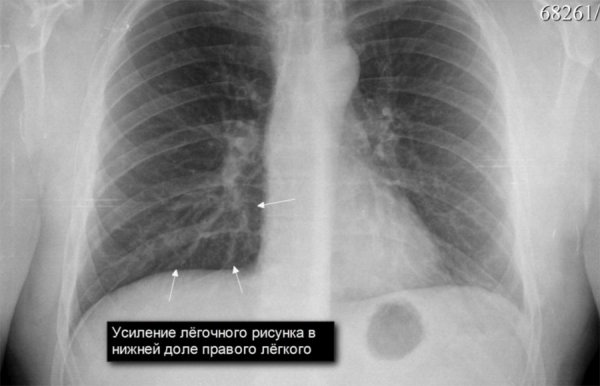

Усиление легочного рисунка - это явление, которое может наблюдаться на рентгеновских снимках грудной клетки. Легочный рисунок представляет собой сетку тонких линий, которые отображают структуру легких. При усилении этого рисунка можно заметить более выраженные и четкие линии, что говорит о повышенной активности дыхательной системы. Это может быть вызвано различными факторами, такими как физическая нагрузка, стресс или патологические состояния, например, воспаление легких или астма. Усиление легочного рисунка является важным признаком для проведения диагностики и определения возможных причин изменений в дыхательной системе.

Усиление легочного рисунка на рентгене